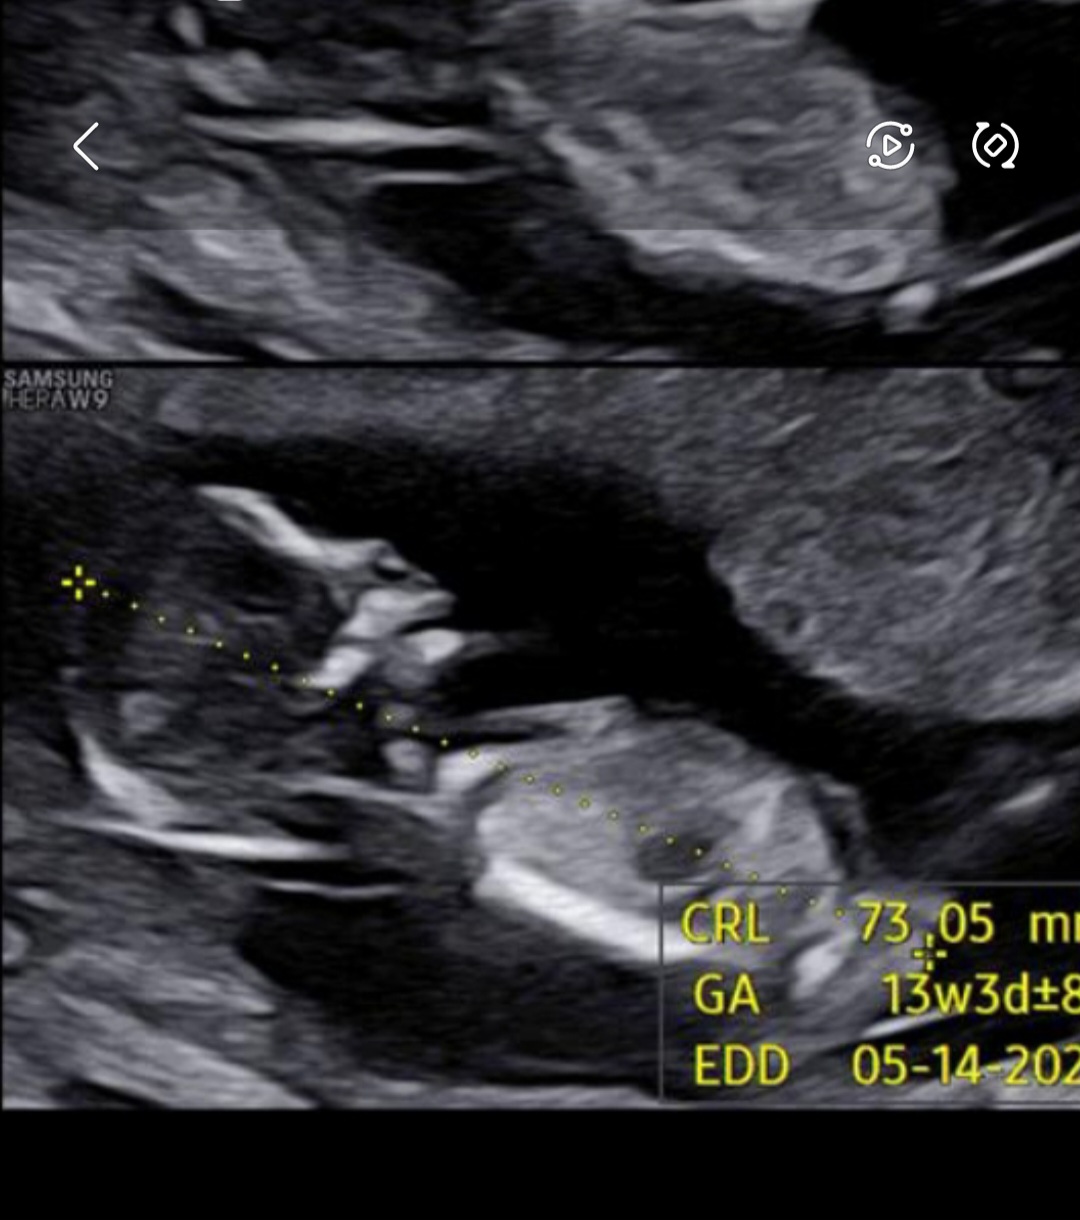

سلام دوستان من ۱۳ و ۳ روز انتی احتمال دختر داد ۱۵ هفته و ۴ رور هم رفتم گفت دختر و نوشت تو جزییات و اینکه ۱۷ هفته ام رفتم سونو گفت دختر دیگ صد در صد مطمعن باشم دیگه؟

۱۷ هفته پوزیشنش سفالیک بود. جنسیت تو اون حالت مشخصه دیگ؟ 😍 باورمون نمیشه تا بغل نگیریمش